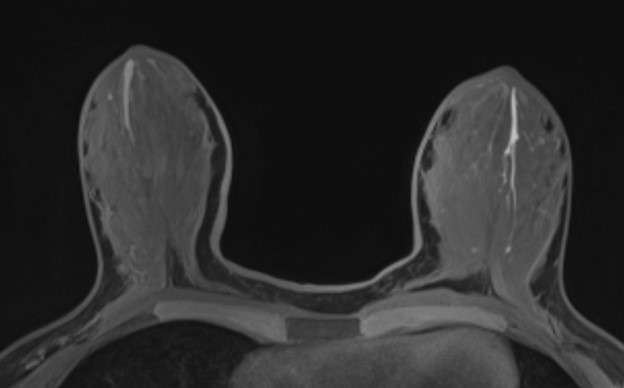

Magnetic Resonance Imaging (MRI) features include:

- Duct ectasia often presents as dilated tubular structures in a specific converging pattern towards the nipple, most often without contrast enhancement on MRI. They commonly exhibit T2 hyperintensity and T1 hypointensity.

- Inflammatory changes surrounding the dilated ducts can also be seen, presenting as increased signal intensity on T2-weighted images with or without enhancement on contrast enhanced images.